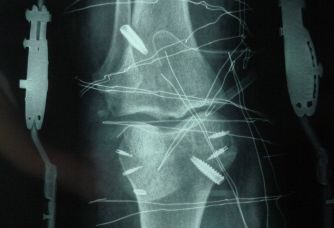

患者刘某,女性,49岁,4个月前因车祸导致双膝韧带损伤,入院后诊断为左膝陈旧性前后交叉韧带损伤,右膝前交叉韧带损伤。由于患者受伤时间较长,韧带3处伤口均已转化为陈旧性损伤,手术难度较大。骨四科燕飞主任在详细问诊后敲定治疗方案:双膝前交叉韧带为自体韧带重建,左膝后交叉韧带为人工韧带重建。经过骨四科全体医护人员的精心准备和严密组织,手术成功。医生通过运用肌腱取出器把找出的半腱肌和股薄肌的肌腱切取、编修,利用关节镜切口(标准)在关节镜的辅助下对韧带的残端运用刨削刀打磨,并作为交叉韧带的止点,接着在屈膝100°区域利用胫骨瞄准器打入导向针,并用空心钻作为胫骨股骨隧道。在Endobutton钢板套环中平分地套上半腱肌和股薄肌肌腱后,通过导针将其植入胫骨股骨隧道,牵引导线,确定钢板处于股骨外侧髁并翻转钢板,预张力合适后用挤压螺钉固定,最后把引流管埋入并缝合。手术耗时4小时10分钟,术后患者功能恢复良好。